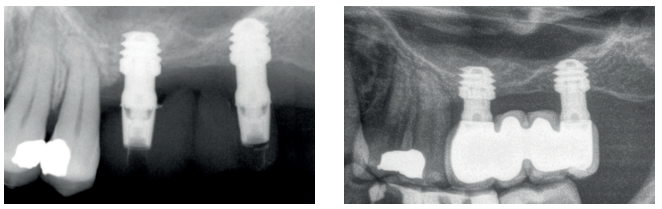

Todos los implantes fueron rehabilitados en dos fases y todos ellos fueron ferulizados a otros implantes en la rehabilitación. En todos los casos se realizó prótesis atornillada de más de un implante con elementos intermedios (transepiteliales), ferulizándose a otros implantes de longitud de 4,5 o 5,5 mm. En todas las situaciones se realizó una prótesis de carga progresiva a los 6 meses de la inserción del implante consistente en una estructura provisional terminada en resina para pasar a una prótesis definitiva metalcerámica. En todos los casos se conservan los transepiteliales iniciales para mantener el hermetismo logrado en la primera fase de la confección de la prótesis.

En las Figuras 2- 19 se muestra uno de los casos incluidos en el estudio.

la oseointegración del implante 6 meses después de la cirugía. Se observa una ganancia ósea de 4 mm.

implante y el volumen óseo ganado y conservado tras la función de los implantes.